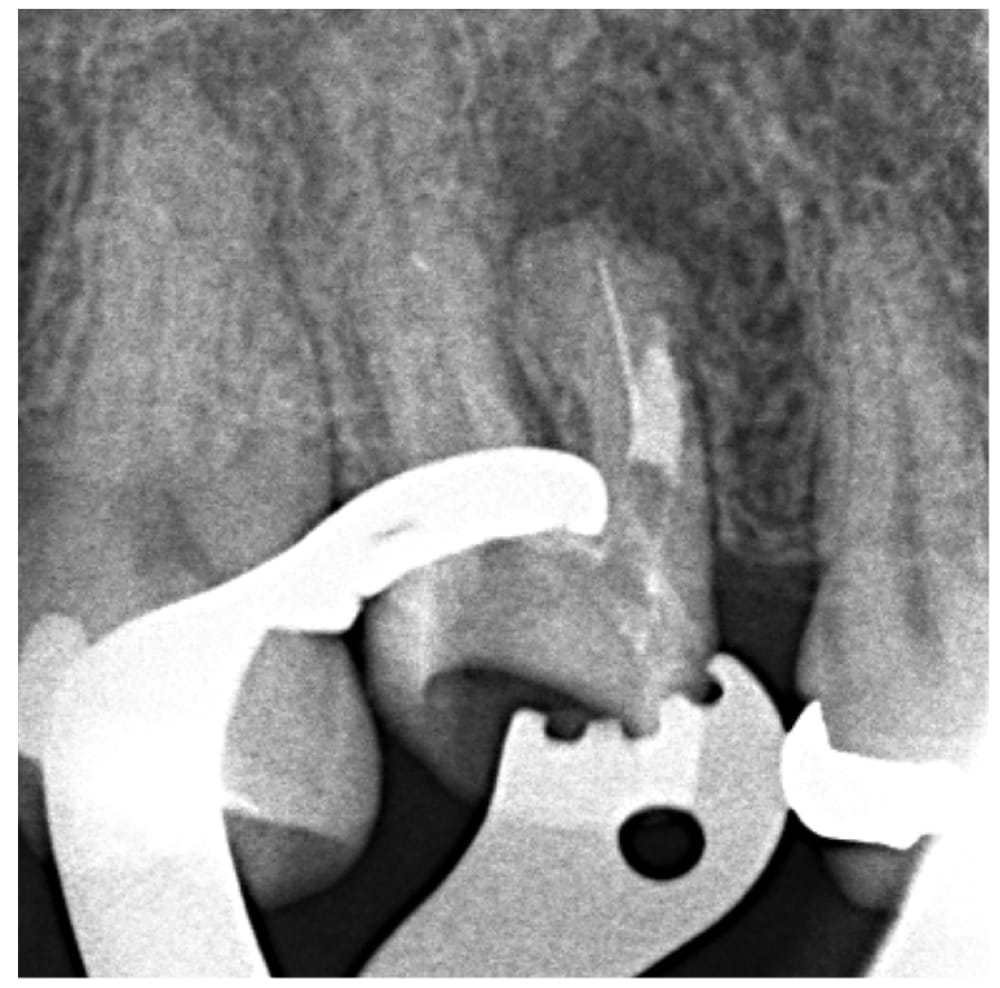

ステップ2

破折ファイル断端の位置を視認した状態を保ちながら、まずはパーフォレーションの部位に対してMTAセメントで封鎖を行いました。これにより、根の中が外部と交通し、持続的な細菌感染が起こることを防ぎます。